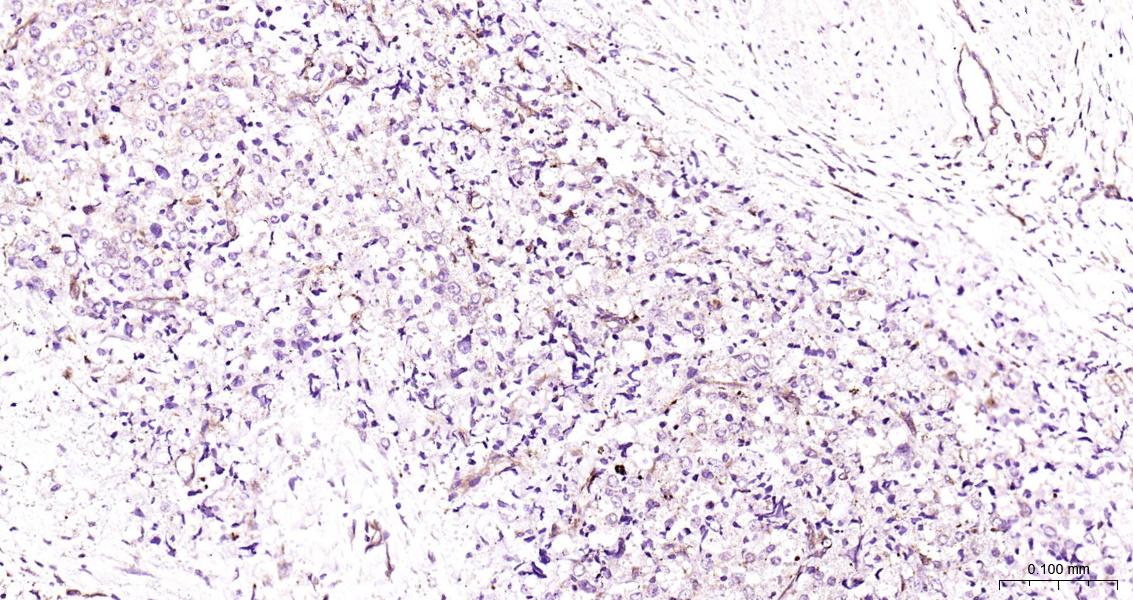

ZO-1 Monoclonal Antibody

Catalog # bsm-41327m

Product Name ZO-1 Monoclonal Antibody

Applications WB, ICC/IF

Reactivity Human

Background The N-terminal may be involved in transducing a signal required for tight junction assembly, while the C-terminal may have specific properties of tight junctions. The alpha domain might be involved in stabilizing junctions. Plays a role in the regulation of cell migration by targeting CDC42BPB to the leading edge of migrating cells.